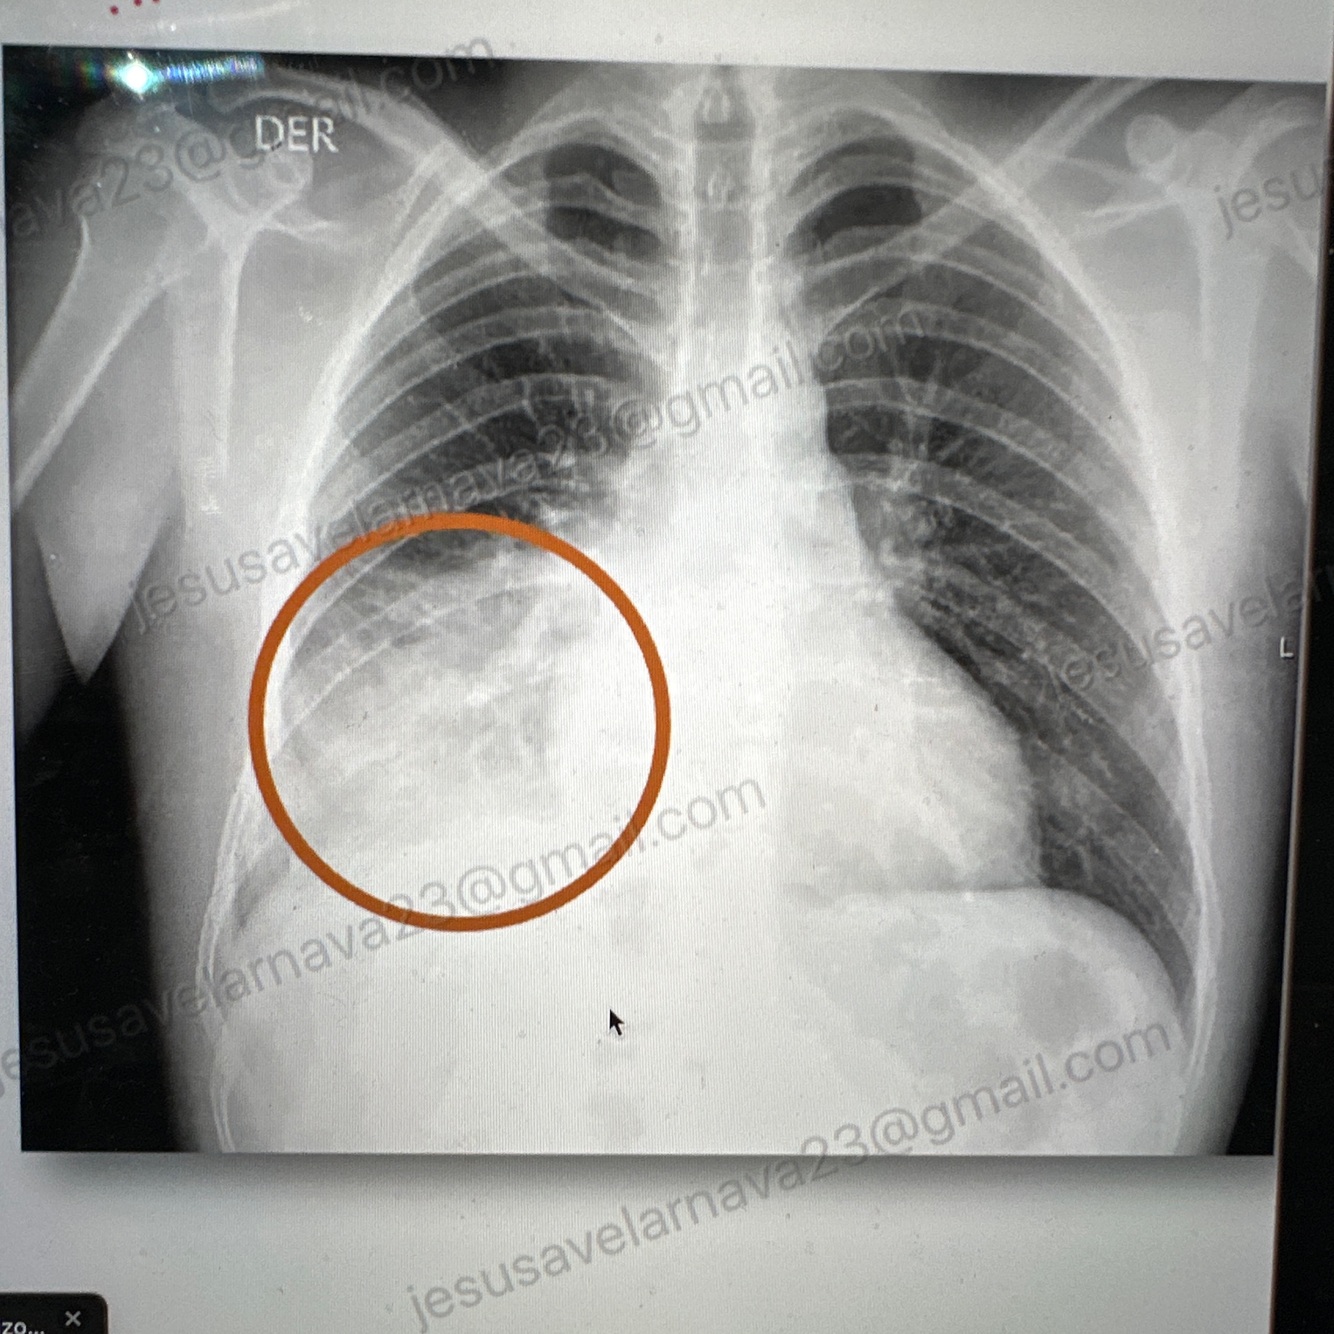

Neumonía típica (un solo lobulo)

Agente #1: S. Pneumoniae